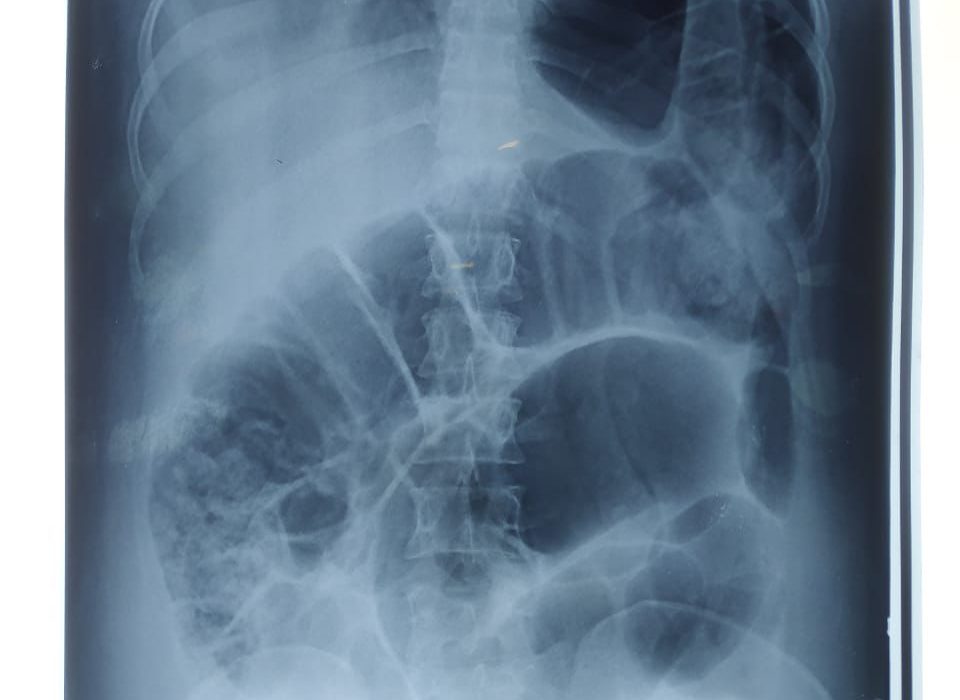

After 48 hours, on her second post operative day her abdomen gradually became distended, bowel sound became absent and suddenly she developped severe respiratory distress. The attending doctor tried with propped up position, oxygen inhalation and intravenous frusemide as it was taken as heart failure but patient was not improving rather became critical within an hour. She became tacypnic, respiratory rate 30 bpm and saturation dropped to 60%.

Then she was shifted to ICU on 17th December. That time her respiratory rate was 30/min, pulse was 120/bpm, blood pressure 110/70 mm of hg, temperature 99 degree fahrenheit , saturation 60%, abdomen distended.On

Auscultation breath sound was absent in left lower zone, diminished in middle and upper zone but normal normal in right side.

On the same day a portable X ray done that shows pnemothorax in left side.

Niddle was inserted in her lt second intercostal space, some air came out of the thorax and patient felt a bit better for sometime only. Again her distress increased which make doctors to bring a second differential diagnosis.

In next morning another X ray done in erect posture that shows hugely distended loop of gut in her left mediastenum that had pushed the left lung upwards.

Finally it was diagnosed as a diaphramatic hernia. Intestinal loops entered into the thoracic cavity and trapped. So her abdomen became distended, lung tissue compressed to the upper zone the left side.